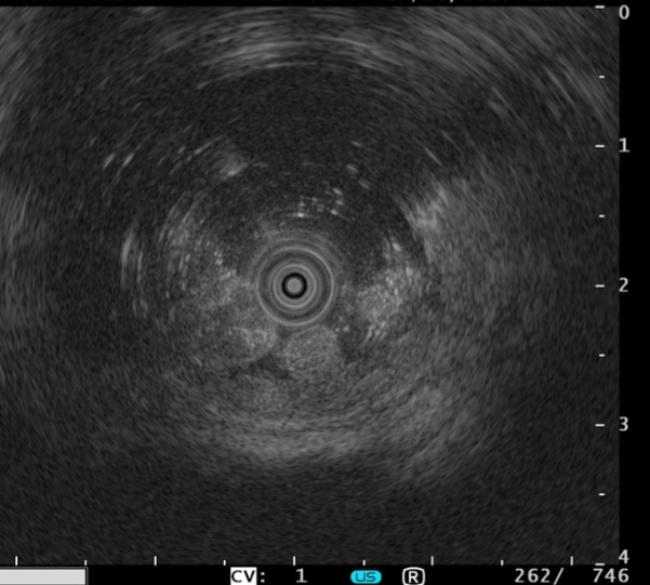

电子结肠镜能直观显示病变的部位、形态及大小(见图2),是临床常用的检查方法。LST,尤其是LST-NG,在常规白光内镜下难以有效检出,漏诊风险较高。因此,普通结肠镜检查中联合其他内镜检查方法不仅能显著提高LST的检出率,还可以借助其他内镜检查对病变的病理类型及浸润深度进行评估。常见的内镜下诊断技术包括放大内镜(magnify endoscopy, ME)联合染色内镜(staining endoscopy, SE)、内镜窄带成像(narrow band imaging, NBI)、蓝色激光成像(blue laser imaging, BLI)、超声内镜(endoscopic ultrasound, EUS)、计算机辅助检测(computer aided detection, CAD)等(见图3图4)。

Figure 4. LST lesion (EUS)

4. LST病变(超声内镜)

该技术是一种将内镜检查与超声成像相结合的检查技术,通过在直视下对病变进行超声扫描,该技术能清晰显示消化道壁的分层结构,并可相对准确地评估其浸润深度[9],对仅凭内镜放大技术无法准确判断病变是否发生浸润的LST病例,可采用超声内镜作为辅助手段以提高诊断准确性。